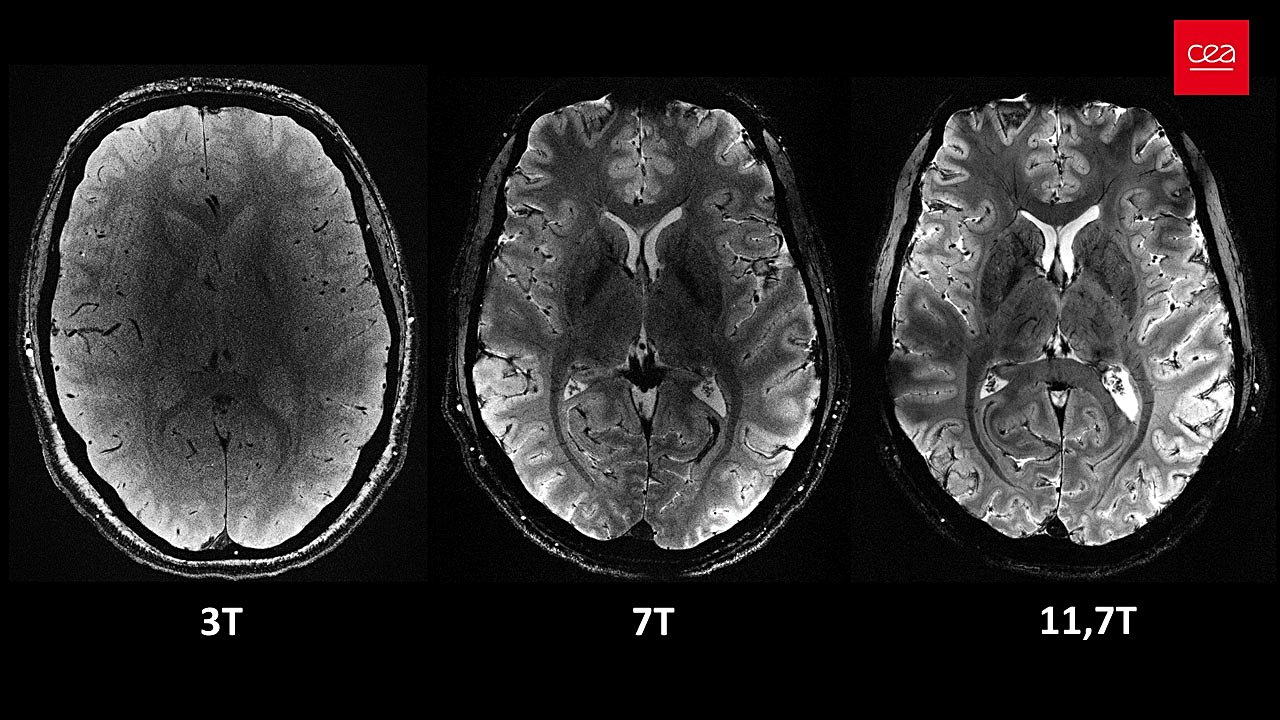

Fransa Atom Enerjisi ve Alternatif Enerjiler Kurumu (CEA) tarafından geliştirilen Iseult MRI makinesi, 11,7 tesla manyetik gücüyle dünyanın en güçlü MRI makinesi olma özelliğini taşıyor. Iseult MRI, hastanelerde bulunan MRI makinelerine göre yaklaşık 4 kat daha güçlü! Hatta kıyaslama olması bakımından, hastanelerde bulunan MRI makineleriyle aynı netlikte bir görüntü oluşturabilmek için saatler harcanması gerekiyor, ki kişi hareket ettiğinde görüntü bulanıklaşacağı için bu pratikte pek mümkün değildir.

Iseult MRI, bahsedilen netlikte bir görüntü oluşturabilmek için sadece 4 dakikaya ihtiyaç duyuyor. Bu görüntülerin beyin hakkında daha önce ulaşılamamış bilgilere ulaşılmasını sağlayacağı öngörülüyor.

Iseult MRI, yüksek manyetik alanı sayesinde düşük sinyalli bazı beyin kimyasalı türlerini de tespit edebiliyor. Bu sayede bu makine ile elde edilen görüntüler ilerleyen yıllarda Alzheimer ve Parkinson gibi nörodejeneratif; bipolar bozukluk ve şizofreni gibi psikiyatrik hastalıkların araştırmalarında etkili olacaktır.